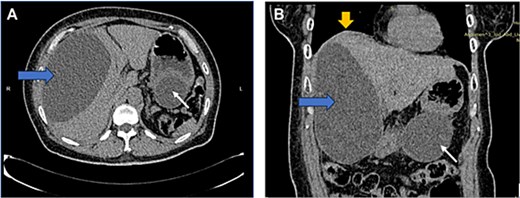

US HBS revealed a cystic lesion in the right liver lobe, raising suspicion for malignancy. OGDS showed a large non-communicating mass, within the distal wall of the greater curvature (Fig. 1). Endoscopic ultrasound (EUS) revealed a well-circumscribed, homogenous stomach cyst (79 × 100 mm). A CT workup was conducted for further clarification, reaffirming the presence of a distinct cystic lesion in the stomach and liver, without signs of malignancy (Fig. 2). At this stage, our findings suggest a large GDC and a coexisting benign hepatic cyst.

CT image: Axial (A) and coronal (B) view showing a well-defined, homogenous cystic lesion (white arrow) arising from the greater curvature of the stomach. Dimensions were ~ 62/79/147 mm with evidence of external compression to the cardia, fundus, and greater curvature. Another large cystic mass (horizontal arrow) originated from the right liver lobe, measuring 91/146/172 mm. Mass effect was noted with superior displacement of the right hemidiaphragm (vertical arrow). No suspicious or aggressive features of these cystic lesions.